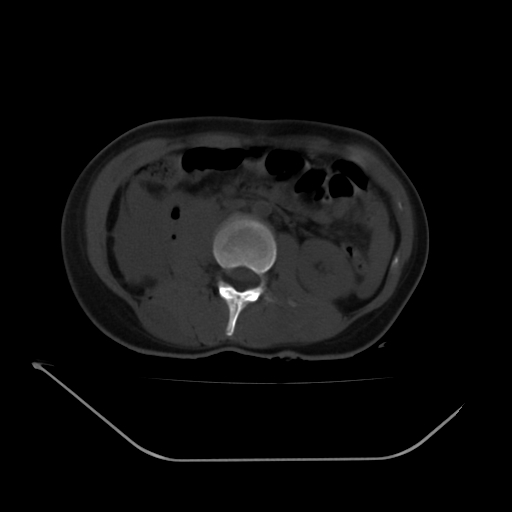

以下是引用liuyue在2008-7-19 13:02:00的发言:[br]1.肝右叶后下段及右肾挫裂伤伴腹腔积血。[br]2.右侧多发性肋骨骨折、横突骨折、右髂骨骨折伴周围软组织挫伤。[br]3.右侧腰大肌肿胀,并可见低密度影,如为气体,则肠道挫裂伤待除外。

以下是引用zhengfaming在2008-7-19 14:42:00的发言:[br]1.肝右叶后下段及右肾挫裂伤伴腹腔积血。脾脏挫裂伤待排[br]2.右侧多发性肋骨骨折、横突骨折、右髂骨骨折伴周围软组织挫伤。[br]3.右侧腰大肌肿胀,并可见低密度影,如为气体,则肠道挫裂伤待除外